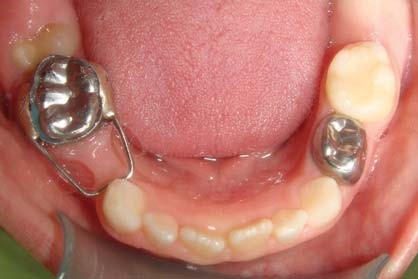

Hàm giữ khoảng là khí cụ được sử dụng để giữ không gian trống trên cung hàm khi trẻ bị mất răng sữa sớm. Thiết bị này giúp ngăn chặn các răng bên cạnh xô lệch vào khoảng trống, từ đó đảm bảo răng vĩnh viễn sau này mọc đúng vị trí.

(Hàm giữ khoảng giúp cho các răng sữa bên cạnh không nghiêng về khoảng trống răng mất)(**)

(Khí cụ giữ khoảng cố định sẽ giúp các răng vĩnh viễn mọc lên đúng hướng)(**)